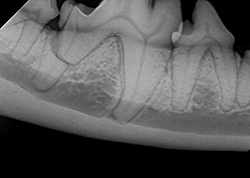

What dental conditions should I look for in my dog?

Jan 29, 2019In addition to gingivitis and periodontal disease, there are some less commonly seen dental conditions that owners should be aware of, such as tooth fractures, tooth root abscess, and caries. -